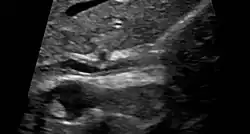

Ultrasound of sclerosing cholangitis in the common bile duct

Various forms of gallbladder disease such as gallstones and gallbladder polyps are also common in those with PSC.[1] Approximately 25% of people with PSC have gallstones.[1] Ultrasound surveillance of the gallbladder every year is recommended for people with PSC.[1] Any person with PSC who is found to have a mass in the gallbladder should undergo surgical removal of the gallbladder due to the high risk of cholangiocarcinoma.[1] Osteoporosis (hepatic osteodystrophy) and hypothyroidism are also associated with PSC.